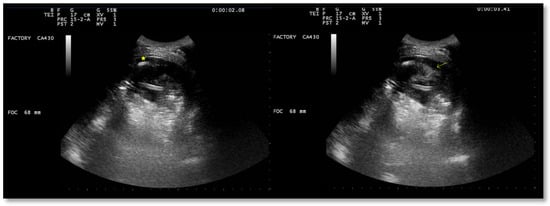

A chest US showed multiloculated PEff with septations of different thicknesses (Figure 9). A 12 Fr chest tube was placed, and 1000 mL of turbid fluid were drained. Samples were collected for microbiological and physicochemical analysis. Irrigation of the pleural cavity with 200,000 IU of urokinase in 50 mL of saline solution was performed under US guidance (Video 1). This was followed by the closure of the chest drain for 3 h, and then it was reopened. Further irrigation with 100,000 IU was performed 24 h later. Empiric antibiotic therapy with 500 mg azithromycin (q24h) for 6 days and 4.5 g piperacillin/tazobactam (q8h) for 2 weeks was administered. A chemical analysis of the pleural fluid revealed exudate. The microbiological study was negative.

Ultrasound observations 48 h after the administration of the first dose of urokinase showed the absence of fibrinous septa and a significant decrease in PEff (Figure 10 and Figure 11).

Figure 9. Chest ultrasound at admission showing multiloculated pleural effusion.

Figure 10. Chest US 48 h after urokinase. Minimum pleural effusion with residual fibrinous material and signs of lung re-expansion.

Figure 11. Chest US 48 h after urokinase. Chest tube in pleural cavity with residual pleural effusion.